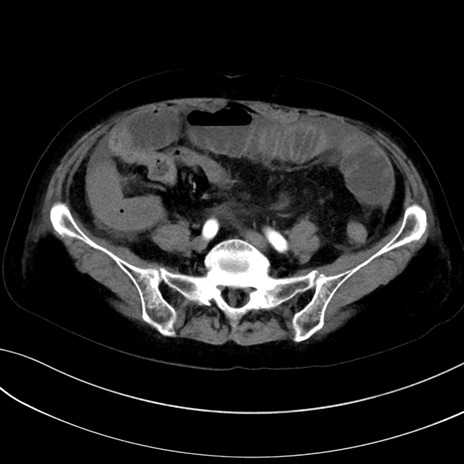

症例13 CT(横断像)1日半後